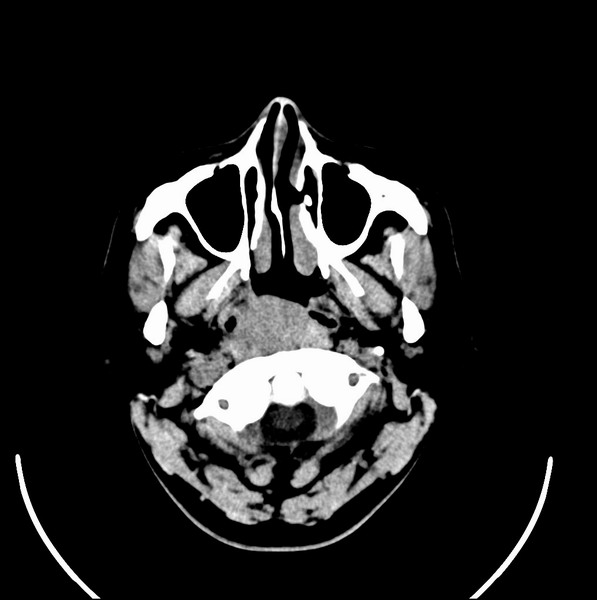

扫描示鼻咽腔不对称,中度狭窄,右侧咽隐窝消失,局部软组织肿块,鼻咽右侧壁增厚形成肿块,突入鼻咽腔,肿块平扫呈等密度,肿块向深部侵润,右侧翼内外肌受侵,右侧咽旁间隙变窄;向后生长,头长肌界线欠清,向后上生长侵犯同侧颈动脉鞘区。双侧海绵窦增宽,内见软组织影与鼻咽部肿块相连。考虑鼻咽癌。鼻咽癌主要是放射治疗,且效果较好;到当地有治疗设备较大医院治疗即可。

这个病例有点特殊,和常见的鼻咽癌不太一样,以向颅内侵犯为主,骨质破坏区小。鼻咽癌首先要考虑,有没有其他可能?本人不会看mr片,期待有人能讲解,期待病理。

鼻咽部新生物(纤维血管瘤?鼻咽癌?)侵犯右侧中颅窝底及右侧海绵窦;建议必要时活检定性。

鼻咽部新生物侵犯右侧中颅窝底及右侧海绵窦,鼻咽癌可能性大。建议增强扫描。纤维血管瘤禁忌穿刺。